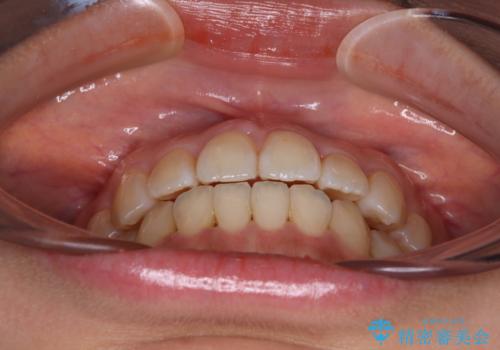

クロスバイトの前歯を改善 ワイヤー装置で楽々矯正治療

舌のトレーニングをしっかりと行っていただき、補綴治療も含めて1年強の短期間で治療を終えることができました。

- 前歯のクロスバイトを改善したいとのことで来院された患者様です。